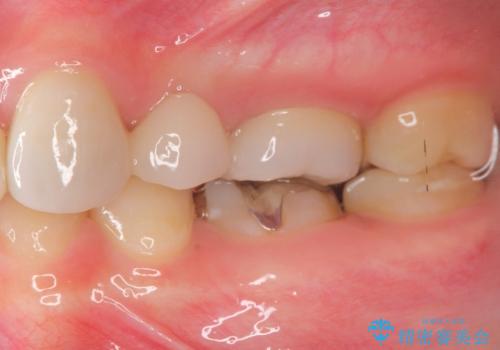

- 保険治療で装着されたかぶせ物と詰め物を変更したいとのことで来院されました。

自然なオールセラミックへ変更することとなりました。

金属を使わないセラミックへ変更することで、自然な見た目になるとともに、ぴったりとした精度の高いかぶせ物を装着することができました。